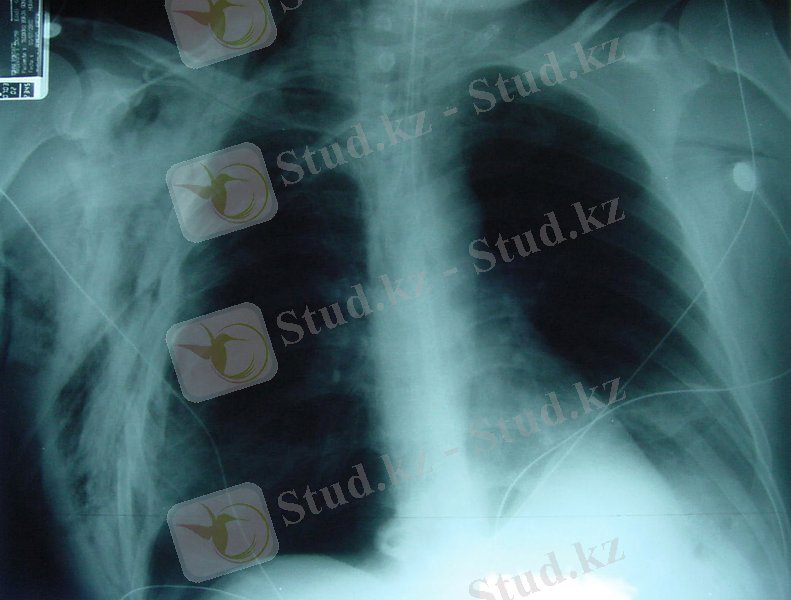

Пневмоторакстың рентгенологиялық белгілері-

- Тері астылық эмфизема- қорытынды рентгенограммада «қабатталған қамыр» түрінде көрінеді (сурет 6), толық тері асты эмфиземасында қабырғалар құрылымы, өкпе тіні нашар жіктеледі, үлкен кеуде бұлшықеті бойымен радиальді «сәулелер» анықталады (сурет 7) .

- өкпеліе суреттің жоғалуымен «ағару» аймақтары (сурет 8)

- өкпе шеті анықталады (сурет 8) .

Сурет 7. Толық тері асты эмфиземасы кезіндегі қорытынды рентгенограмма. Қабырға құрылымдары, өкпе тіні нашар жіктеледі, үлкен кеуде бұлшықеті бойымен радиальді «сәулелер» көрінеді.

Сурет 8. Пневмоторакс кезінде қорытынды рентгенограмма:

Сызықтармен өкпе суреті және өкпе шеті жойылған «ағарған» бөліктері көрсетілген.